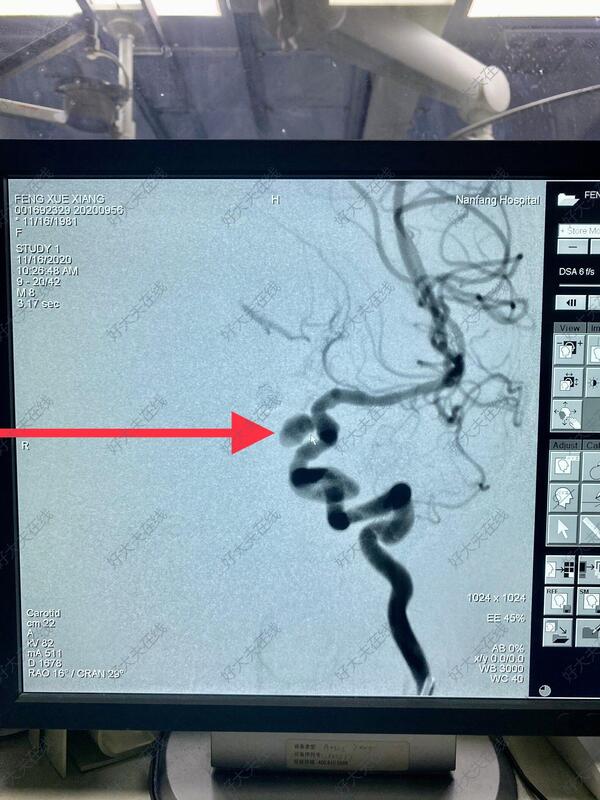

治疗前

血管迂曲,血管内介入路径困难。而且动脉瘤已经破裂,颅内高压,首选微创治疗,创伤小,恢复快